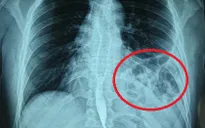

Ngày 12/9: Thêm 2.013 ca mắc COVID-19 mới; 1 ca tử vong tại Hải Phòng - Ảnh 1.